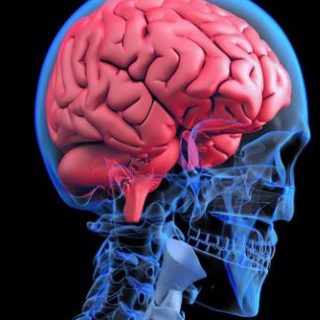

U pacientů po chemoterapii se může urychlit stárnutí mozku, což je spojené s poklesem mozkových funkcí. To se často pojí s tvorbou a ukládáním patologických bílkovin, např.

Roztroušená skleróza je autoimunitní onemocnění, které poškozuje centrální nervovou soustavu, tj. mozek a míchu, neboť dochází ke ztrátě myelinu, který chrání hlavní nervové výběžky. V